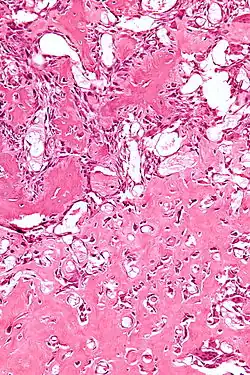

| Micrograph of an osteoblastoma H&E stain | |

The cause of osteoblastoma is unknown. Histologically, osteoblastoma are similar to osteoid osteomas, producing both osteoid and primitive woven bone amidst fibrovascular connective tissue, the difference being that osteoblastoma can grow larger than 2.0 cm in diameter while osteoid osteomas cannot. Although the tumor is usually considered benign, a controversial aggressive variant has been described in the literature, with histologic features similar to those of malignant tumors such as an osteosarcoma.[4]